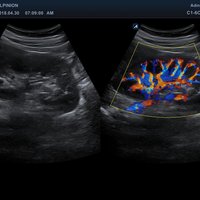

• Farbdoppler: farbige Darstellung der Richtung des Blutflusses

• Powerdoppler: sensitive, farbige Darstellung des Blutflusses unabhängig von Geschwindigkeit und Richtung

• DPDI: Technologie, die Sensitivität des Powerdopplers mit der Flussrichtungsinformation des konventionellen Farbdopplers kombiniert